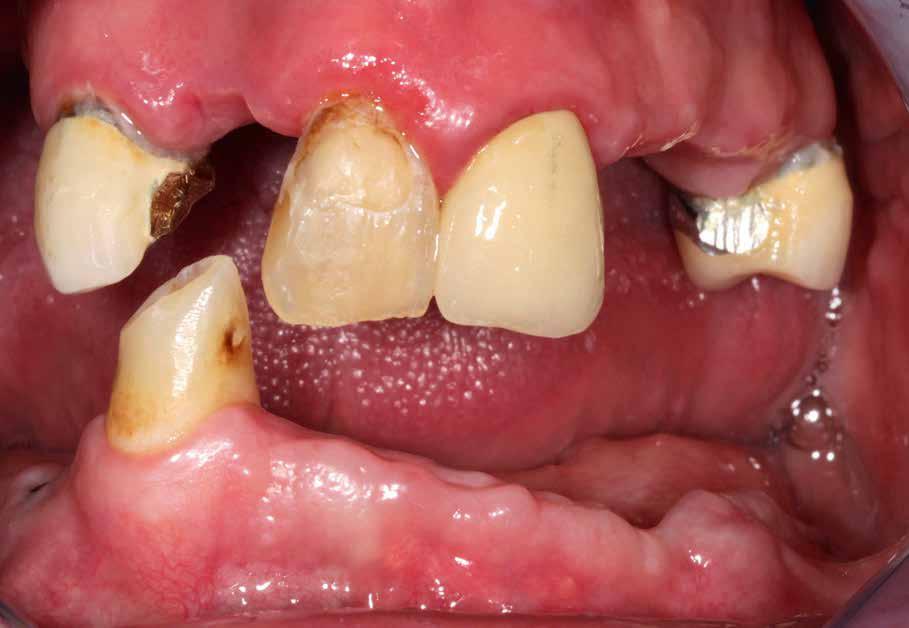

Középkorú páciens, felül négy maradék fog, alul egy szemfog (2. kép). Olyan pótlást akartunk készíteni, amelyik a maximálisan elképzelhető ideig nyújt elégedettségre okot adó komfortot. Ehhez mi a teleszkópoknak szinte utánozhatatlan alkalmazását látjuk megoldásnak. A teleszkóp szilárd,

2. kép: Megtartandó maradékfogazat.

A páciens

A 49 éves páciens kb. 19 éves hidakkal érkezett a rendelőbe, amelyek már problémát jelentettek számára. „Hexagonális ellátási koncepciónk” ezen első fázisában – anamnézis – a páciens elmeséli panaszait, és ismerteti a kezelésre vonatkozó elvárásait. Ennek alapján állítjuk össze a kezelési tervet, amelyet a következő ülésben, a fogtechnikus jelenlétében ismertetünk vele. Esetünkben 400 km a távolság a labor és rendelő között, melynek következtében a fogtechnikus Facetime-on (Skype) keresztül volt jelen. Így a páciens a teljes csapattal megismerkedett, a fogtechnikus képernyő segítségével bemutathatta a megoldási variációkat, és a minőségi különbségek részleteit is ismertethette.

A páciens teleszkópos hidak mellett döntött (ódzkodunk a fogsor szó használatától, mivel a híd attraktívabb megoldásnak értékelődik).

Felül elégségesnek tűnt a négy megmaradt fog pillérként, az állkapocsba azonban pillérnek további három implantátum beültetését javasoltuk a stabilitás érdekében.